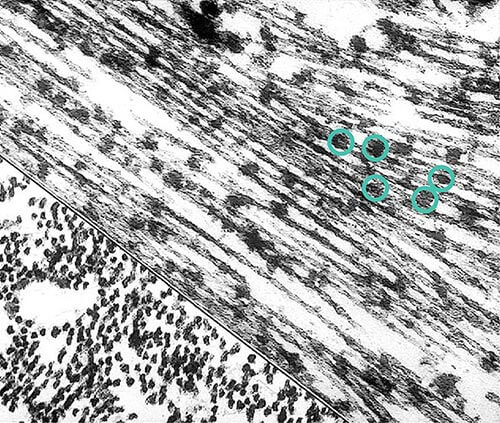

More About Tangles

Tangles destroy a vital cell transport system made of proteins. This electron microscope picture shows a cell with some healthy areas and other areas where tangles are forming.

In healthy areas:

In areas where tangles are forming:

Nutrients and other essential supplies can no longer move through the cells, which eventually die.